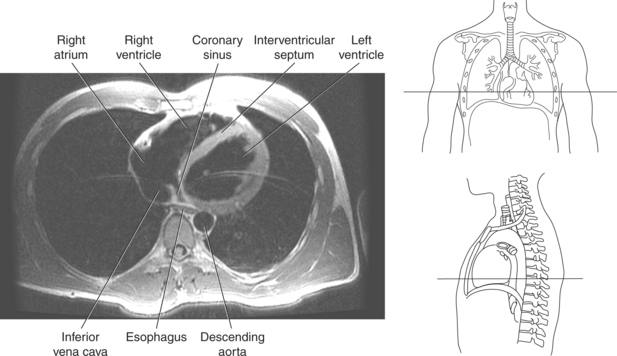

The heart is a hollow, four-chambered muscular organ located within the middle mediastinum. It is approximately the size of a large clenched fist and is situated obliquely in the chest with one third of its mass lying to the right of the median plane and two thirds to the left. The heart can be described as being roughly trapezoid shaped (Figure 6.33). The superficial relationships of the heart include the base, apex, three surfaces (sternocostal, diaphragmatic, pulmonary), and four borders (right, inferior, left, and superior). The broad base (posterior aspect) is the most superior and posterior portion of the heart. It is formed by both atria, primarily the left atrium, and gives rise to the great vessels. The apex is formed by the left ventricle and points inferiorly, anteriorly, and to the left. It is located at the level of the fifth intercostal space, just medial to the midclavicular line. The sternocostal (anterior surface) is formed primarily by the right atrium and right ventricle with a small contribution from the left ventricle. The diaphragmatic (inferior surface) rests on the central tendon of the diaphragm and is formed by both ventricles and a small portion of the right atrium. The pulmonary (left surface) is formed mainly by the left ventricle and fills the cardiac notch of the left lung. The borders of the heart represent the external surfaces of the cardiovascular silhouette in radiographic profile. The borders include the right border, formed by the right atrium and located between the superior and inferior venae cavae; the left border, formed by the apex of the heart or the left ventricle; the superior border, formed by the right and left atria; and the inferior border, which is formed primarily by the right ventricle with a small contribution from the left ventricle (Figures 6.33 through 6.35).

The walls of the heart consist of three layers: (1) epicardium, the thin outer layer that is in contact with the pericardium; (2) myocardium, the thick middle layer consisting of strong cardiac muscle; and (3) endocardium, the thin, endothelial layer lining the inner surface. The endothelial layer also lines the valves of the heart and is continuous with the inner lining of the blood vessels. The heart is divided into four chambers: the right and left atria and the right and left ventricles. The two superior collecting chambers called atria are divided by the interatrial septum. During embryonic development an oval opening exists within the interatrial septum called the foramen ovale. This opening allows blood flow between the right and left atria during fetal lung development. At birth, the foramen ovale closes, leaving a small depression in the septal wall called the fossa ovalis in the adult heart. The two inferior pumping chambers called ventricles are divided by the interventricular septum (Figure 6.39).

The right atrium forms the right border of the heart and receives deoxygenated blood from the body via the superior and inferior venae cavae and from the coronary sinus and cardiac veins that drain the myocardium. A small muscular embryonic appendage, the right auricle, projects upward and toward the left from the right atrium, covering the root of the aorta (Figure 6.40). The right ventricle lies on the diaphragm and comprises the largest portion of the anterior surface of the heart. It receives deoxygenated blood from the right atrium and forces it into the pulmonary trunk for conveyance to the lungs. Projecting off the inferior surface of the ventricular walls are conical-shaped projections of cardiac muscle called papillary muscles that anchor the cusps of the tricuspid valve to the right ventricle (Figure 6.39). The left atrium lies posterior to the right atrium and is the most posterior surface of the heart. It also has an embryonic appendage, the left auricle, that projects to the left of the pulmonary trunk over the superior surface of the heart. The left atrium receives oxygenated blood directly from the lungs via the four pulmonary veins (two on each side). The left ventricle forms the apex, left border, and most of the inferior surface of the heart. It receives oxygenated blood from the left atrium and pumps it into the aorta for distribution throughout the systemic circuit. The myocardium of the left ventricle is normally three times thicker than that of the right ventricle, reflecting the force necessary to pump blood to the distant sites of the systemic circulation (Figures 6.41 through 6.52). Two papillary muscles project from the ventricular walls to anchor the bicuspid valve to the ventricle (Figures 6.39 and 6.47).